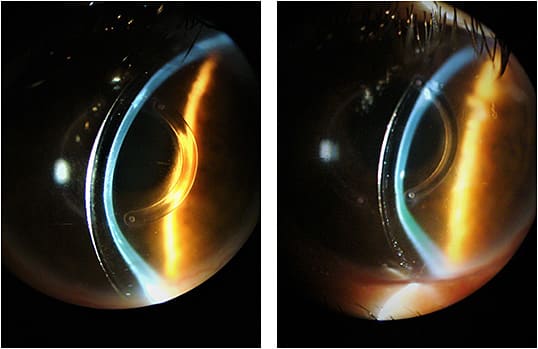

A higher vault may be tolerated in some cases, especially when you fit the larger, full scleral lenses that have diameters of 18mm and greater. But an excessive vault may also result in corneal hypoxia and subsequent corneal edema. Figure 3 shows the lens vault at presentation.

Figure 4 shows the fluorescein pattern at presentation using biomicroscopy with a cobalt blue filter OS.

In this case, the patient mentioned seeing a rainbow, indicating that corneal edema was present. The limbus was affected, and we noted superficial keratitis in both eyes.